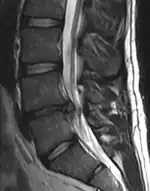

![]() |

![]() | |

The straight leg raise test can detect pain originating from a herniated disc. When warranted, imaging such as MRI can provide clear detail about disc related causes of back pain (L4–L5 disc herniation shown) | ||

Este indicată efectuarea unor radiografii în cazul existenței unor semnale de avertizare, simptome neurologice persistente care nu dispar sau dureri constante ori agravante.[8] În special, utilizarea timpurie a radiografiilor (IRM sau CT) este recomandată în cazul în care pacientul este suspectat de cancer, infecții sau sindromul cozii de cal.[8] Imagistica prin rezonanță magnetică (IRM) este ușor mai bună decât testele CT pentru a identifica bolile de coloană - cele două tehnologii sunt la fel de utile pentru a diagnostica stenoza spinală.[8] Numai câteva teste de diagnosticare fizică sunt utile.[8] Testul de elongație femurală iese aproape întotdeauna pozitiv la persoanele cu hernie de disc.[8] Discografia lombară stimulată poate fi utilă pentru a identifica un anumit disc care provoacă durere persoanelor cu niveluri ridicate cronice de durere lombară.[23] În mod similar, procedurile terapeutice, precum blocajele nervoase, pot fi folosite pentru a identifica o anumită sursă de durere.[8] Unele probe încurajează utilizarea injecțiilor în articulațiile fațetate, injecțiilor epidurale transforaminale și a injecțiilor sacroiliace ca metode de testare a diagnosticului.[8] Majoritatea celorlalte teste fizice, precum evaluarea scoliozei, slăbiciunea musculară sau wastingul muscular, precum și reflexele afectate au o utilitate redusă.[8]